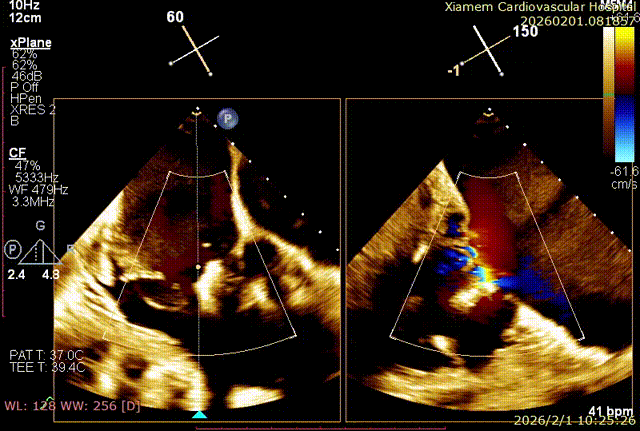

第一个夹子释放后,在前叶、隔叶间靠近中央区仍有残余反流,所以决定再植入一枚 6mm 夹合器。第二枚夹合器抓捕瓣叶过程中,受到第一枚夹合器影响,无法清晰的在 X-plane 切面上进行瓣叶捕获,因此改用 3D-MultiView 切面顺利抓捕,关闭夹合器后残余反流已经由术前极重度(4+)减小为轻中度(2+),手术过程流畅,手术结果完美。

first clip食道中段切面

first clip食道胃底切面

3D-MultiView引导手术